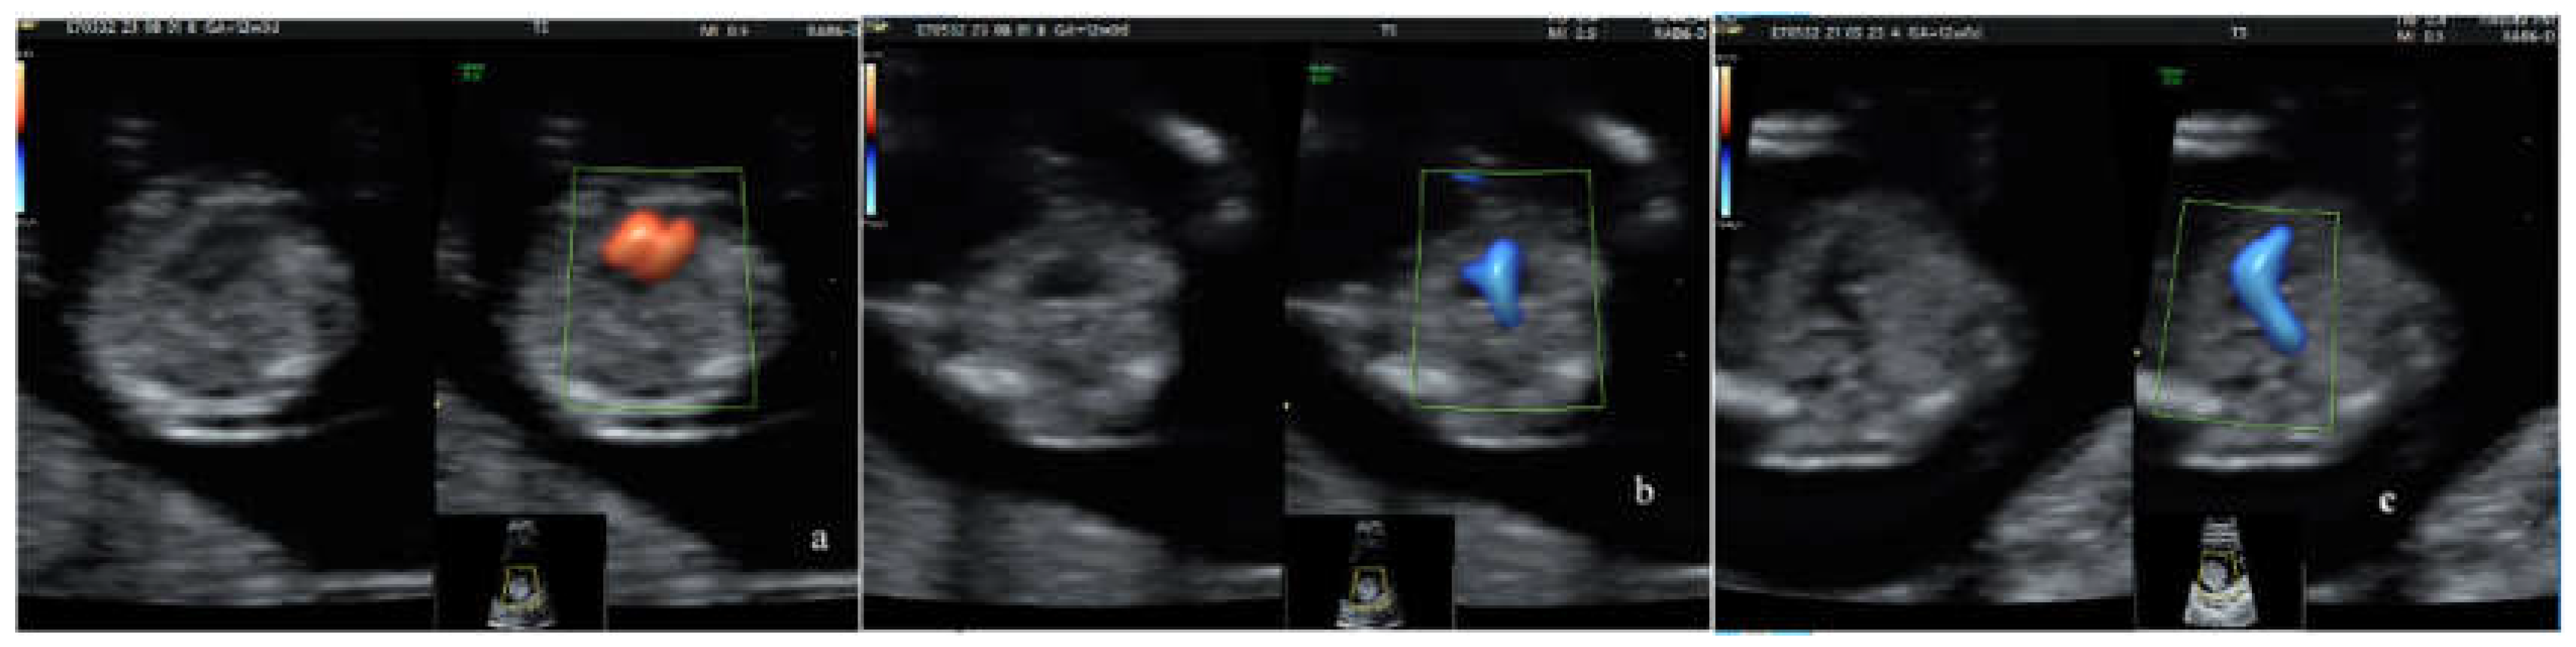

- normal 4-chamber view, normal equal ventricular inflows, in a normal case

- b. confluence of the arches on the left (”the V-sign” in the 3VT view) in a normal case

- c. the ”reverse boomerang sign” - the reverse curvature of right ventricle outflow tract (RVOT) at level of the 3VT view in a TGA case